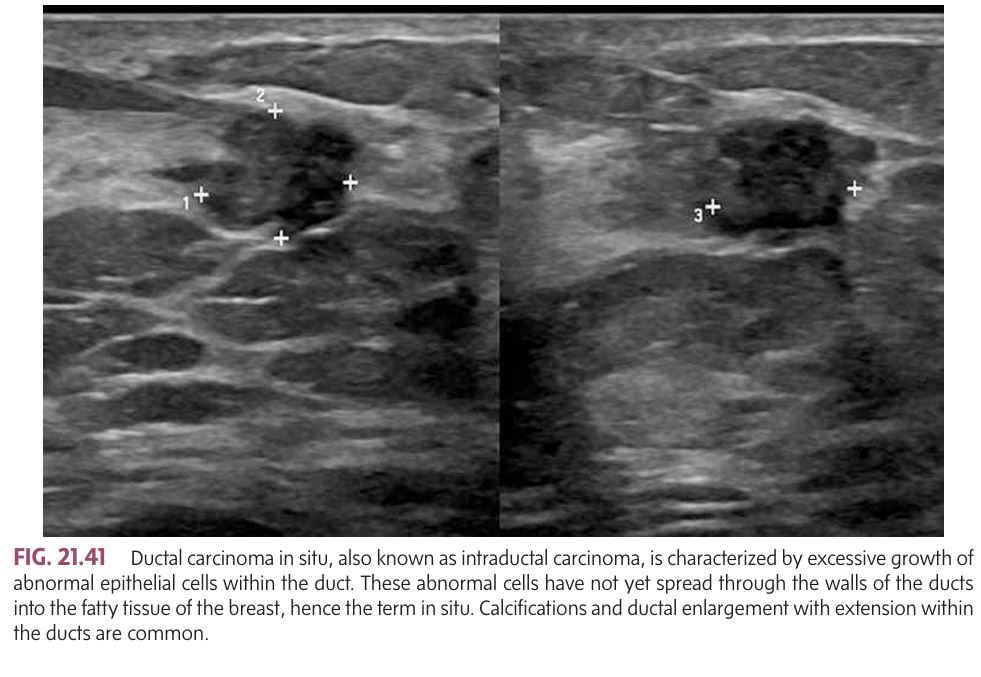

Also known as intraductal carcinoma and is the most common noninvasive breast malignancy.

Description: Non-invasive; cancer cells are confined to the ducts and haven't spread to surrounding tissue.

Signs & Symptoms:

Asymptomatic in many cases.

Nipple discharge (may be bloody).

Some cases may cause a palpable mass.

Imaging Findings:

Microcalcifications (small white specks on mammography).

Ductal enlargement on imaging.

Grading: Can be classified as low, intermediate, or high nuclear grade; higher grades are more aggressive.